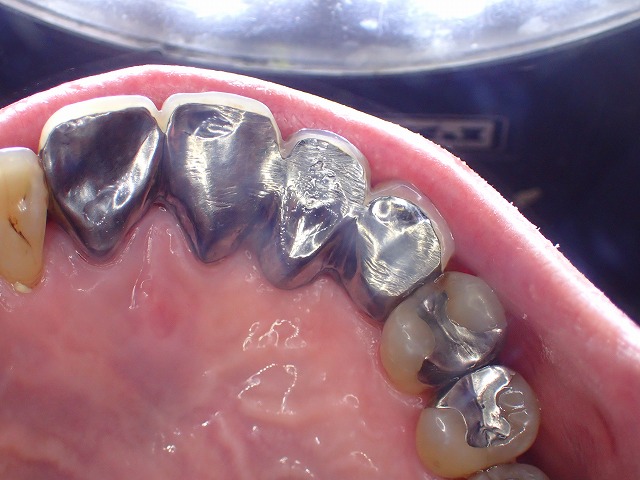

金属の歯では、その摩耗の軌跡が比較的わかりやすく残るため、

このページでは、金属に刻まれた歯ぎしりの跡をもとに解説します。

金属の歯に残る摩耗痕を見ると、前後運動、左右運動、その場での細かな動きなど、顎の動きの特徴がわかることがあります。

金属面Iに歯ぎしりの軌跡

一方向への往復運動が強く、

歯ぎしりで金属を切り落としたように

削れているパターンです。

金属の詰め物や被せ物には、歯ぎしりによる削れ方や摩耗の跡が比較的わかりやすく残ることがあります。

その跡を見ることで、前後に動くタイプなのか、左右に大きく動くタイプなのか、ある場所で噛みしめながら細かく動いているのかなど、顎の動きの特徴を推測しやすくなります。